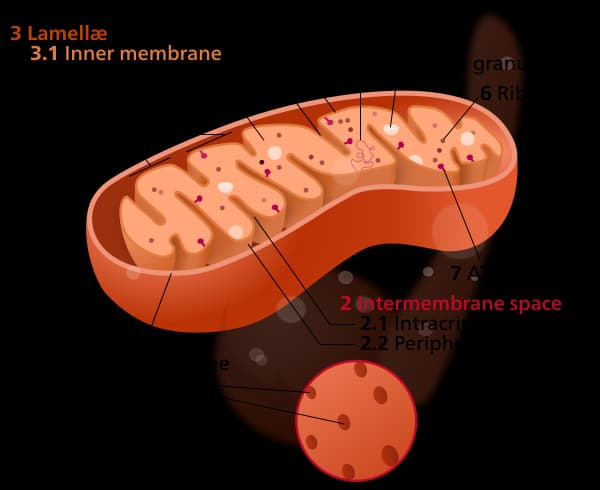

1. Reduce Mitochondrial Function

As I explained last post, PPIs work by limiting the full energy production of cell mitochondria. Naturally, taking too many PPIs will cause lasting effects on how well your mitochondria can function in the future. As a result, decreased mitochondrial function has been linked to almost every disease and underscores all the issues I’ll describe below. For a bit more on the effects of damaging your mitochondria with common drugs, see my post last week about NSAIDs